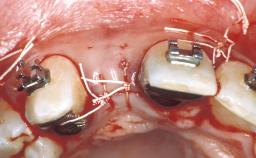

Surgical SAC classification

Surgical SAC Modifiers

| Periodontal Status | - |